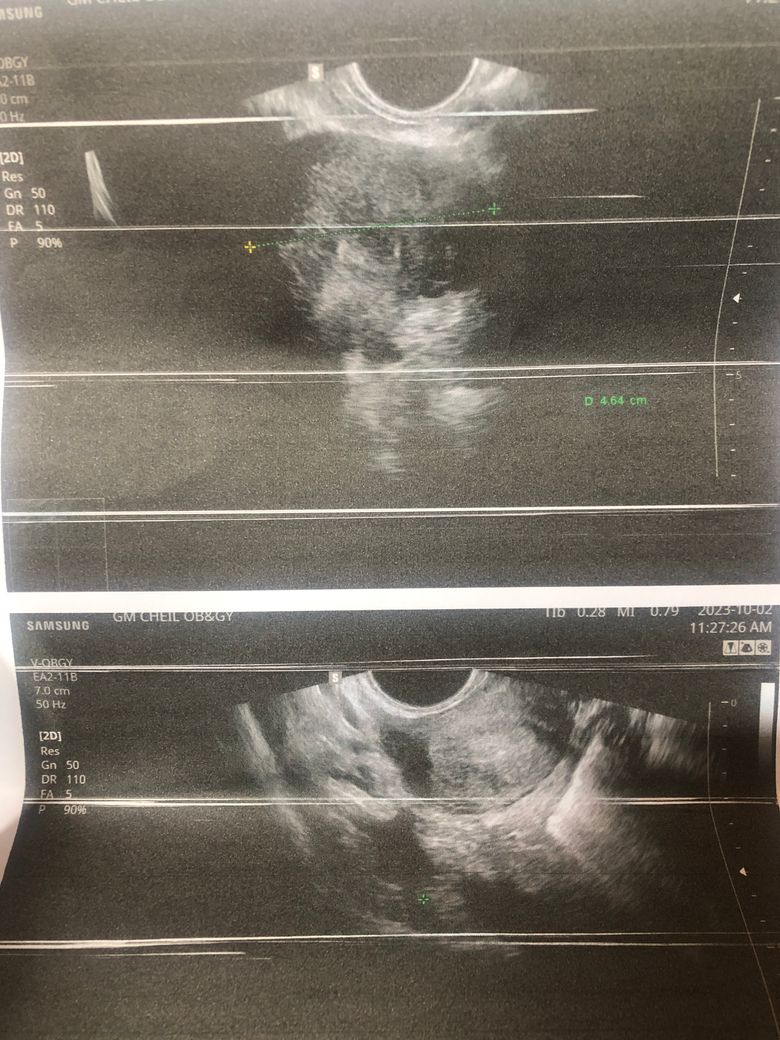

산부인과 검사 했는데요 혹이 있다고 해서 수술해야 한다고 하는데 꼭 수술밖에 답이 없나요?ㅠ(자궁쪽은 아닌거 같고 어디에 난 혹인지 정확히 모르겠다고 합니다)

• 1번 째 사진

• 골반 내부의 혹이 11cm나 된다면 크기가 매우 큰 것입니다. 현실적으로 수술적으로 제거하는 것이 가장 합리적이고 적절한 판단으로 보입니다만, 정확한 것은 큰 병원에서 추가적으로 정밀 검사를 하고 자세하게 파악한 뒤 새롭게 판단 받으시는 것이 좋겠습니다.